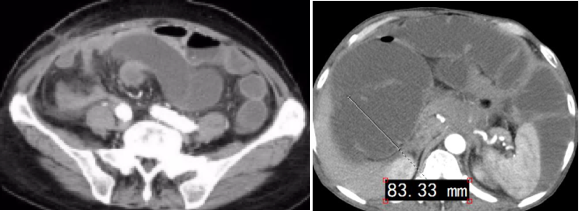

腸梗阻時,由于腸道內(nèi)容物無法正常通過,受阻部位以上的腸管會逐漸擴張。在腹部X線片中,可以觀察到腸管的直徑增大,通常小腸直徑超過3厘米,大腸直徑超過5厘米即為擴張。這種擴張現(xiàn)象在CT檢查中可以清晰顯示,并且CT檢查還可以進一步顯示擴張腸管內(nèi)的氣體和液體分布情況。

在擴張的腸管內(nèi),由于氣體和液體的分層作用,會出現(xiàn)液氣平面。這是腸梗阻的一個重要特征。在站立位或側(cè)臥位的腹部X線檢查中,可見到多個液氣平面,即腸腔內(nèi)的液體與氣體分界面。正常情況下,液氣平少而且短,而在腸梗阻時,液氣平多而且長。CT檢查能更清晰地顯示液氣平大小和形態(tài),有助于確定腸梗阻的位置和程度。

由于腸道內(nèi)壓力升高,腸壁會發(fā)生水腫,表現(xiàn)為腸壁增厚、模糊不清。這一現(xiàn)象在CT檢查中容易觀察到。

在嚴重的腸梗阻病例中,由于腸道內(nèi)壓力持續(xù)升高,可能導(dǎo)致腹腔內(nèi)液體滲出,形成腹腔積液。這一現(xiàn)象在CT檢查中更容易發(fā)現(xiàn)。

● 小腸梗阻:影像學檢查可發(fā)現(xiàn)梗阻部位有魚骨刺狀的表現(xiàn),腸系膜出現(xiàn)漩渦等征象。

● 結(jié)腸梗阻:在影像學檢查中可清楚看到結(jié)腸袋影,在腹部X線檢查中看到扭轉(zhuǎn)部位出現(xiàn)鳥嘴狀特征。結(jié)腸腫瘤堵塞導(dǎo)致腸梗阻時,在梗阻的近端可見明顯的腸管增粗,管內(nèi)有較多糞便等征象。

腸梗阻的影像表現(xiàn)具有多樣性,包括腸管擴張、液氣平面增多、腸壁水腫與增厚、腹腔積液以及特殊類型的腸梗阻表現(xiàn)等。這些影像表現(xiàn)對于腸梗阻的診斷和治療具有重要的指導(dǎo)意義。